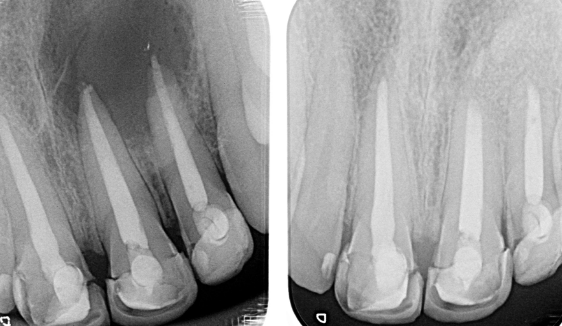

Recuperación ósea

FORMACIÓN DE ENDO-HUESO: IMPORTANCIA DEL PAPEL DE LA ENDODONCIA EN LA REGENERACIÓN DE HUESO. Dr. Borja Zabalegui.